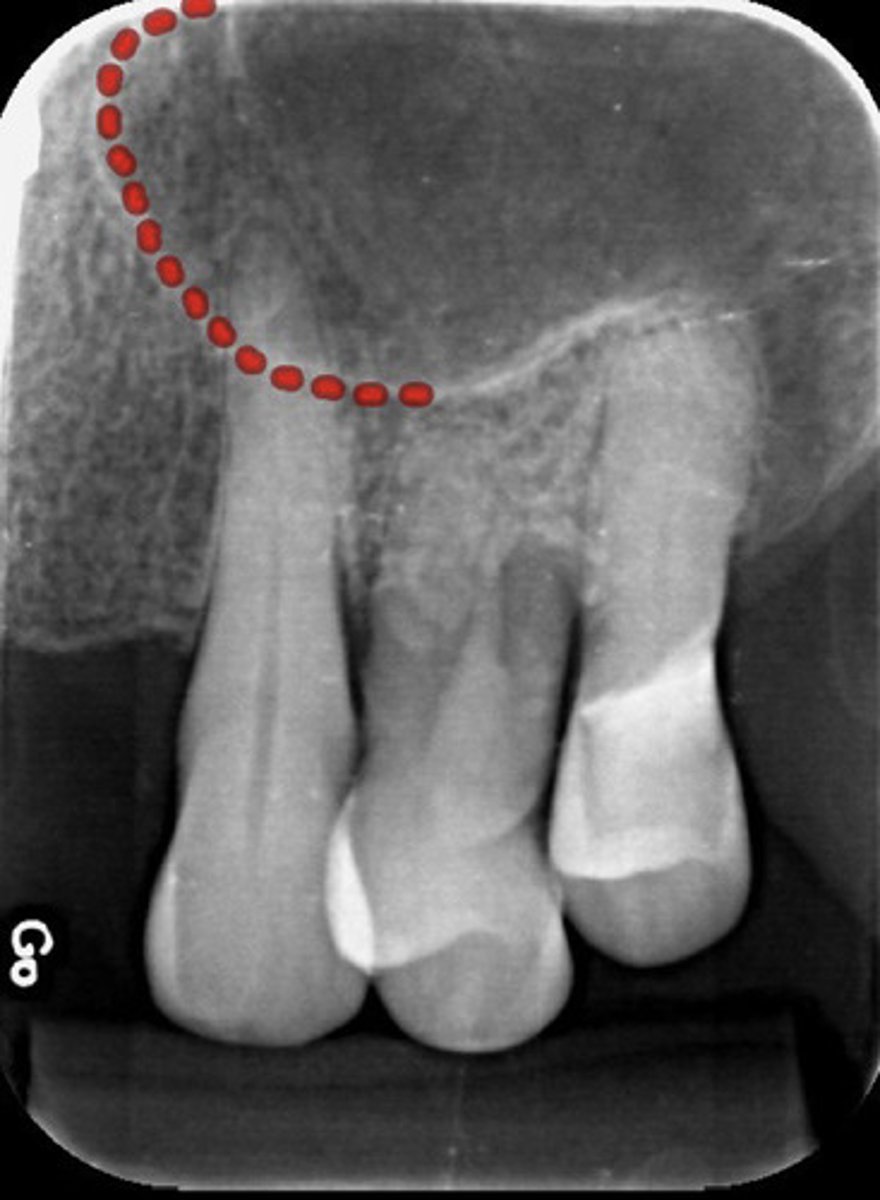

What is the red dotted line representing?

Alveolar extension of the maxillary sinus

-pneumatization